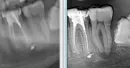

Последнее обследование и лечение у меня происходило ровно 2 года назад. По счастливой случайности, сохранился снимок, теперь можно сравнивать (хотя качество так себе) слева образец от 2018 года, справа от 2020 года.

4 года назад в 36-ом зубе пролечили каналы после скола, а в 37-ом зубе залечили глубокий кариес. После этого зубы не беспокоили никак. В этом году решил разобраться с другой проблемой. При визуальном осмотре врач не увидел проблем, сказал, что пломбы стоят хорошо, но после панорамного снимка сказал, что необходимо перелечивать канал в 36-ом и депульпировать 37-й зуб. В попытках разобраться я посетил ещё 2-х врачей и получил диаметрально разные рекомендации. Один рекомендовал не делать ничего и наблюдать, потому что однозначно сказать нельзя. Второй стал настаивать на перелечивании 36-го и немедленном удалении 37-го зуба.

Каналы в 36-ом зубе перелечивать нет необходимости, но, так как разрушена большая часть коронки зуба, для исключения трещины, следует анатомическую форму восстановить ортопедической конструкцией (вкладка, коронка).

В области периапикальных тканей 37-го зуба имеется разряжение, но, причиной может быть дистопированный и ретинированный восьмой зуб.